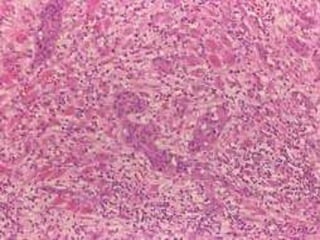

Linfoma

Adenoma pleomorfo  Tumormás frec. de glándulas salivales  Predomina en parótida  7% salivales menores  En cav.oral: 50% de gl. Salivales menores  Cavidad oral: Paladar  Crecimiento lento  Masa firme, dolorosa no ulcerada  Sin cápsula  4a. a 6a. década  Pero a cualquier edad